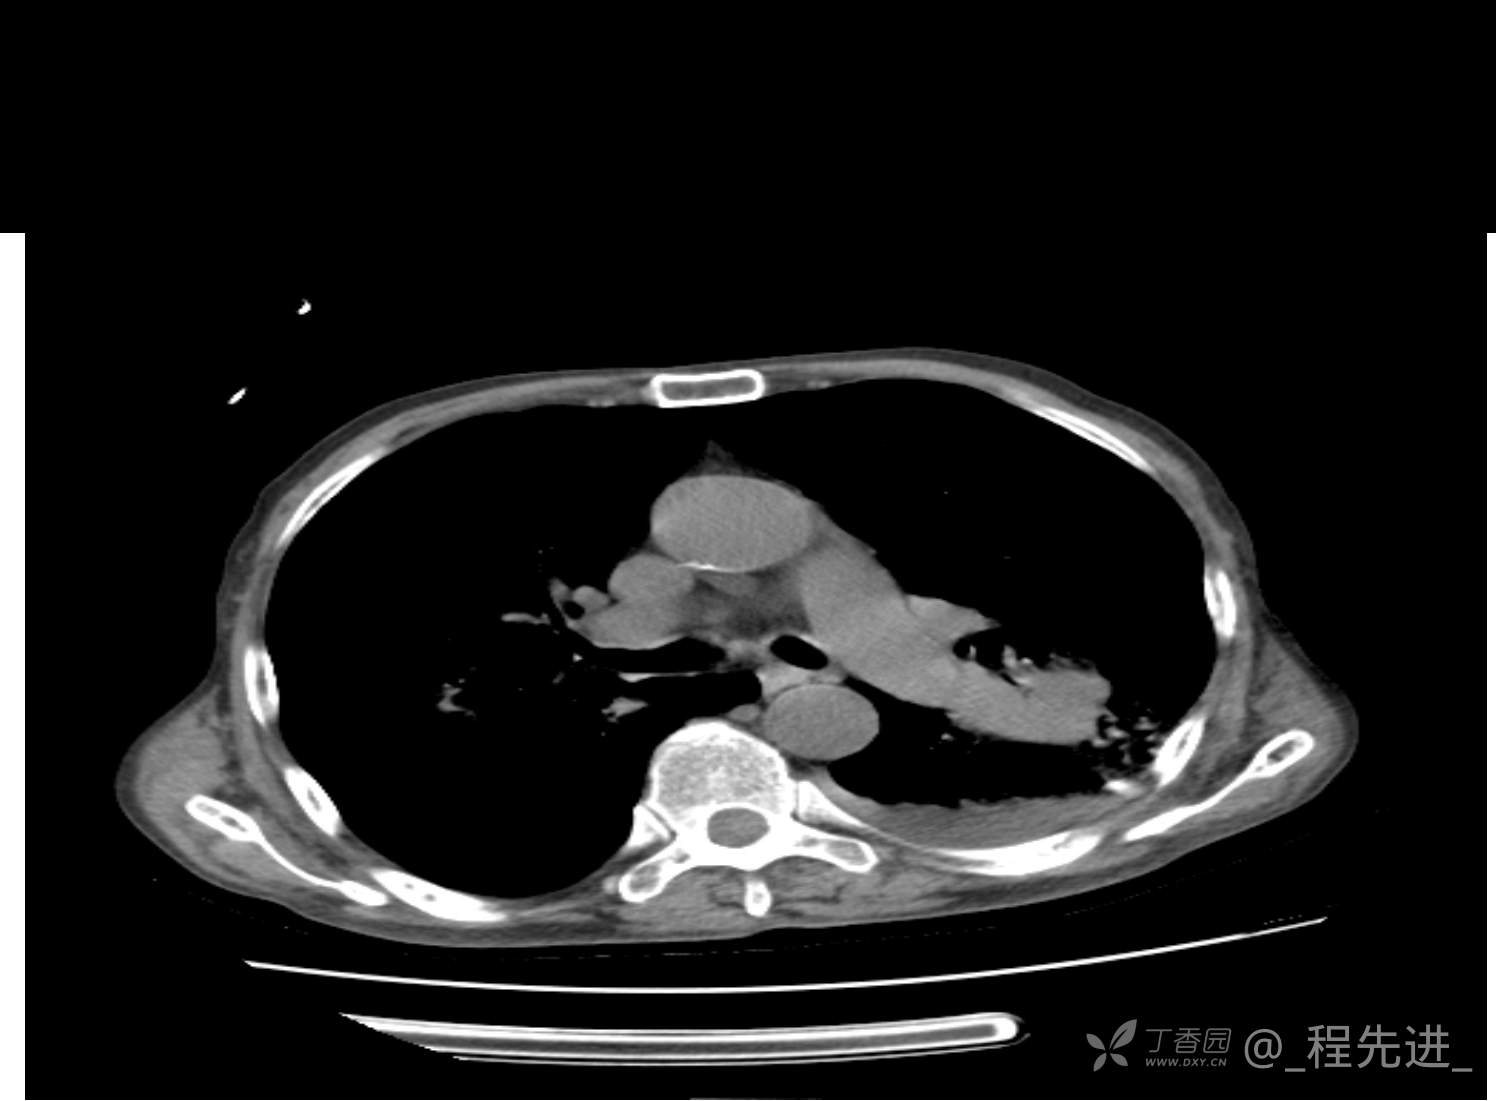

患者性别:男

患者年龄:81岁

简要病史:反复咳嗽、咳痰20余年,加重1周。两肺呼吸音低,可闻及散在干湿啰音。